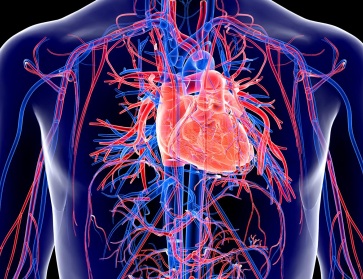

Cardiac Surgery

Vascular

Cardiovascular